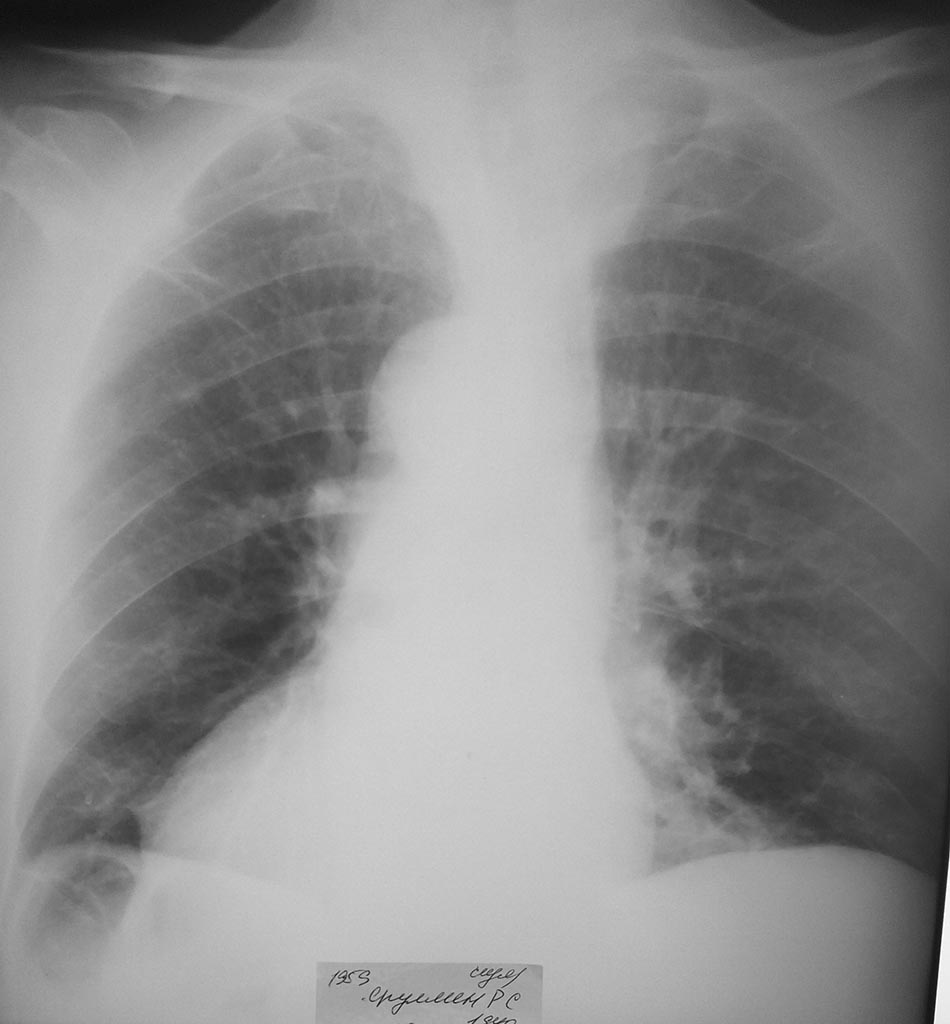

Важными маркерами воспаления являются СОЭ и С-реактивный белок, причем последний лучше определять не в плюсах, а в единицах. В целом представленные показатели крови вроде бы неплохие. Надо выяснять, что дает температуру. Что местно? Гиперемия, отек, боли в месте вмешательства могут быть симптомами раннего нагноения, тогда- ревизия. Иногда длительную температуру дают гематомы, тромбофлебиты. Чтобы исключить пневмонию желательно сделать качественные снимки легких и пригласить терапевта. В любом случае есть необходимость в пролонгированной антибиотикотерапии.

КТ